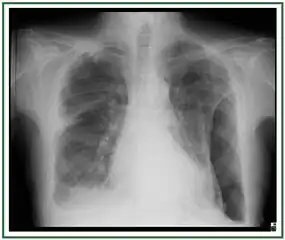

CXR of an individual affected by fibrothorax (consequence of tuberculosis)